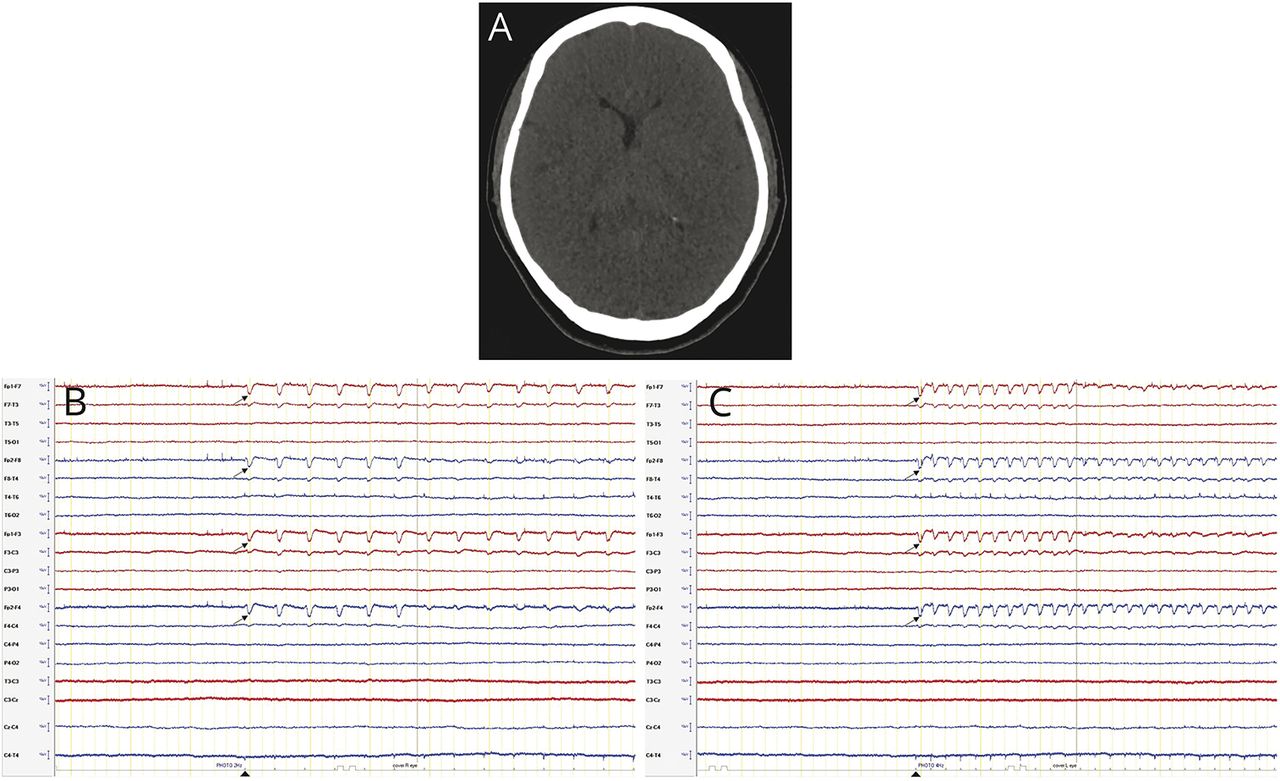

后一个47岁的女人被一个心脏按压心脏骤停。在演讲中,病人的格拉斯哥昏迷评分是3。脑CT显示反演的灰白色密度和弥漫性脑水肿严重缺氧缺血性脑损伤和脑电图显示一致electro-cerebral活动在整个记录与寿命electroretinographic (ERG)放电光刺激(图)。认识到排放ERG工件而不是大脑反应光刺激或光瞬目反射是至关重要的,以避免误导神经预测。1,2后者的作品点出2排放可能会错误地认为一个功能完整的丘脑-皮质网络和脑干,分别。

图

CT脑和纵向双蒙太奇

(一)脑CT显示弥漫性脑水肿和损失正常灰白色的分化。(B, C)纵向双蒙太奇(2μV / mm灵敏度)显示electroretinographic (ERG)工件从视网膜去极化(箭头)引起的光刺激(箭头)。交替的左眼和右眼的阻止视网膜刺激,消灭ERG排放,首先在Fp2 (B),然后在Fp1 (C),确认这些波形的眼来源。